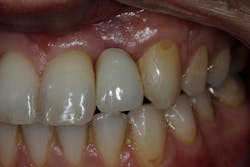

These alveolar bone changes often compromise implant placement due to thin bone volume (figures 2a–2d).

Reduction in quantity and quality of bone can also compromise functional and esthetic outcomes of both implants and fixed bridge restorations (figures 3 and 3a).